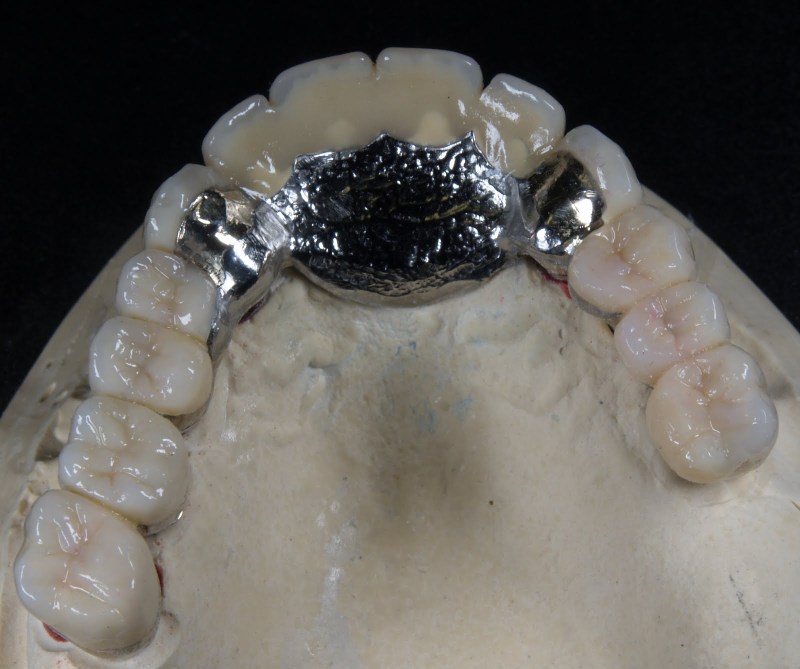

Vom Langzeitprovisorium zur TEK 1 Arbeit